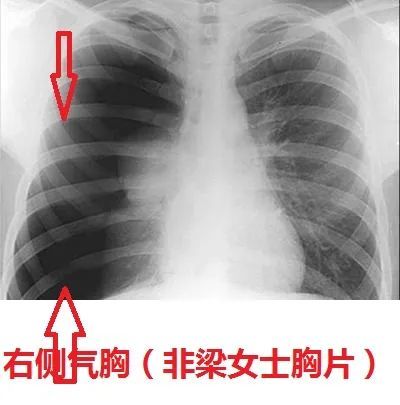

临床挑战——哮喘患者突发胸痛,原因为何?

胸片看到的跟急诊科医生听诊器听到的是符合的,医生听到梁女士左侧